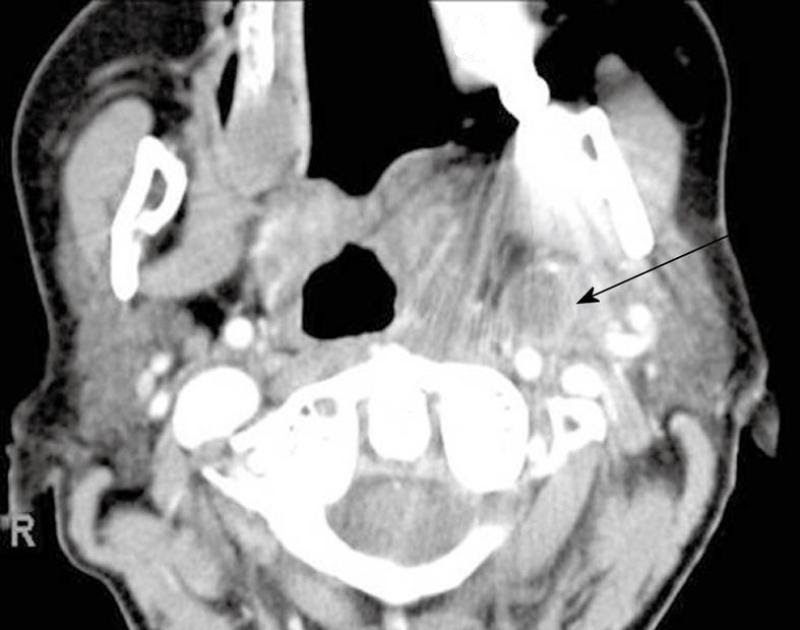

From www.researchgate.net

CT scan of head axial view showing right parapharyngeal abscess What Is Parapharyngeal Abscess Symptoms include fever, sore throat, odynophagia, and swelling in the neck down. a parapharyngeal abscess is a deep neck abscess. Symptoms include fever, sore throat, odynophagia, and swelling in the neck down. It is a serious medical condition, potentially fatal, and. a parapharyngeal abscess is a deep neck abscess. a parapharyngeal abscess is a painful collection of. What Is Parapharyngeal Abscess.